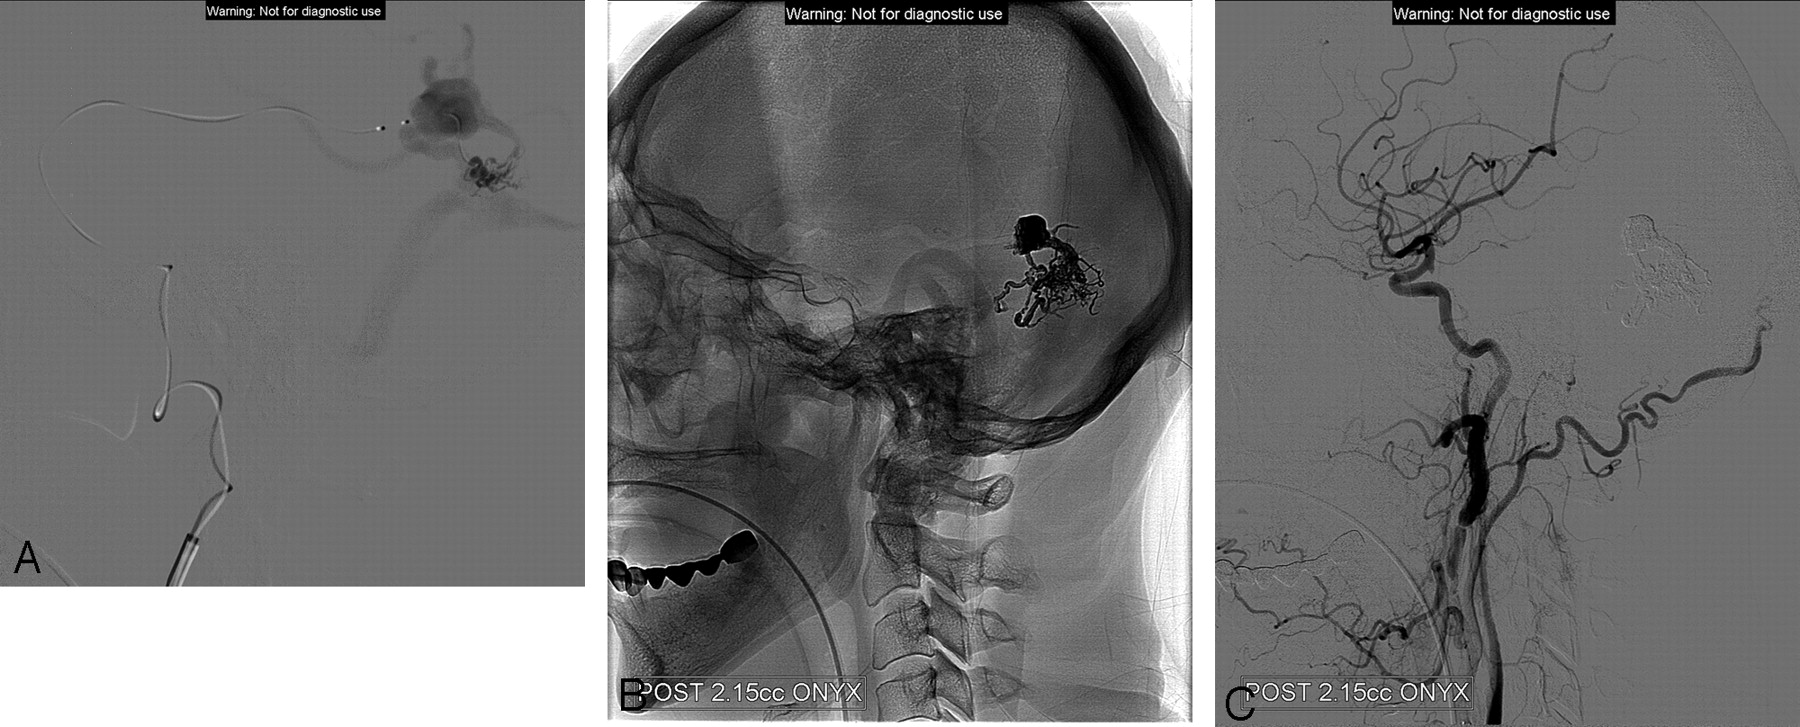

Left lateral common carotid artery. A DAVF fed mainly by middle meningeal branches draining to cortical veins with a varix.

A, Superselective injection with the Sonic microcatheter. Image demonstrates the fistula and the pial cortical draining vein with the varix, draining to the vein of Labbe. B, The final cast includes the proximal part of draining vein and the network of feeders. C, The completion injection and full closure of the fistula.